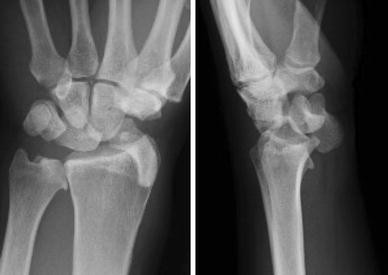

Fig. 1

figure 1

Radiographs at initial diagnosis showing palmar-divergent dislocation of the scaphoid and lunate

A 46-year-old man who fell from a height of 1.5 m onto his left hand was brought to the emergency center of our hospital and underwent a medical examination. Radiography of the wrist revealed palmar-divergent dislocation of the scaphoid and lunate (Fig. 1) but with no neurovascular disturbance in the hand. Two hours after the injury, we performed closed reduction under local anesthesia. Although closed reduction was successful, severe carpal instability was observed. Seven days after the injury, open surgery was performed through the palmar and dorsal approaches. The dorsal approach showed ruptures of the scapholunate and lunotriquetral ligaments, which were sutured with anchors. The palmar approach showed an oblique tear of the anterior capsule, which was sutured with absorbable threads. Finally, the scapholunate and lunotriquetral joints were fixed with two Kirschner wires, inserted from the scaphoid to the lunate and from the triquetrum to the lunate, respectively, and the wires were buried under the skin (Fig. 2). A short arm plaster splint was applied postoperatively; 2 weeks later, it was changed to a removable splint and rehabilitation was started. As Kirschner wires remained in the carpal bones, range of motion (ROM) exercises of the wrist were restricted to avoid wire failure. At 7 weeks, the Kirschner wires and splint were removed, and the patient was started on intensive rehabilitation for an additional 3 months. At the 1-year follow-up, the patient had returned to normal life and work and had no pain in his wrist, although wrist motion was still restricted. Measurements of wrist and forearm ROM showed that right/left extension was 60/50°, flexion was 70/40°, supination was 90/80°, and pronation was 90/90°. A hand dynamometer showed that grip strength in his left hand was 16 kg compared with 27 kg on the contralateral (dominant) side. Although we observed no evidence of dorsal or volar intercalated segment instability pattern deformity, radiography showed a break in arc II of Gilula’s line between the lunate and triquetrum, as well as flexion deformity of the scaphoid (Fig. 3) [8]. Magnetic resonance imaging showed no evidence of avascular necrosis of the scaphoid and lunate (Fig. 4).